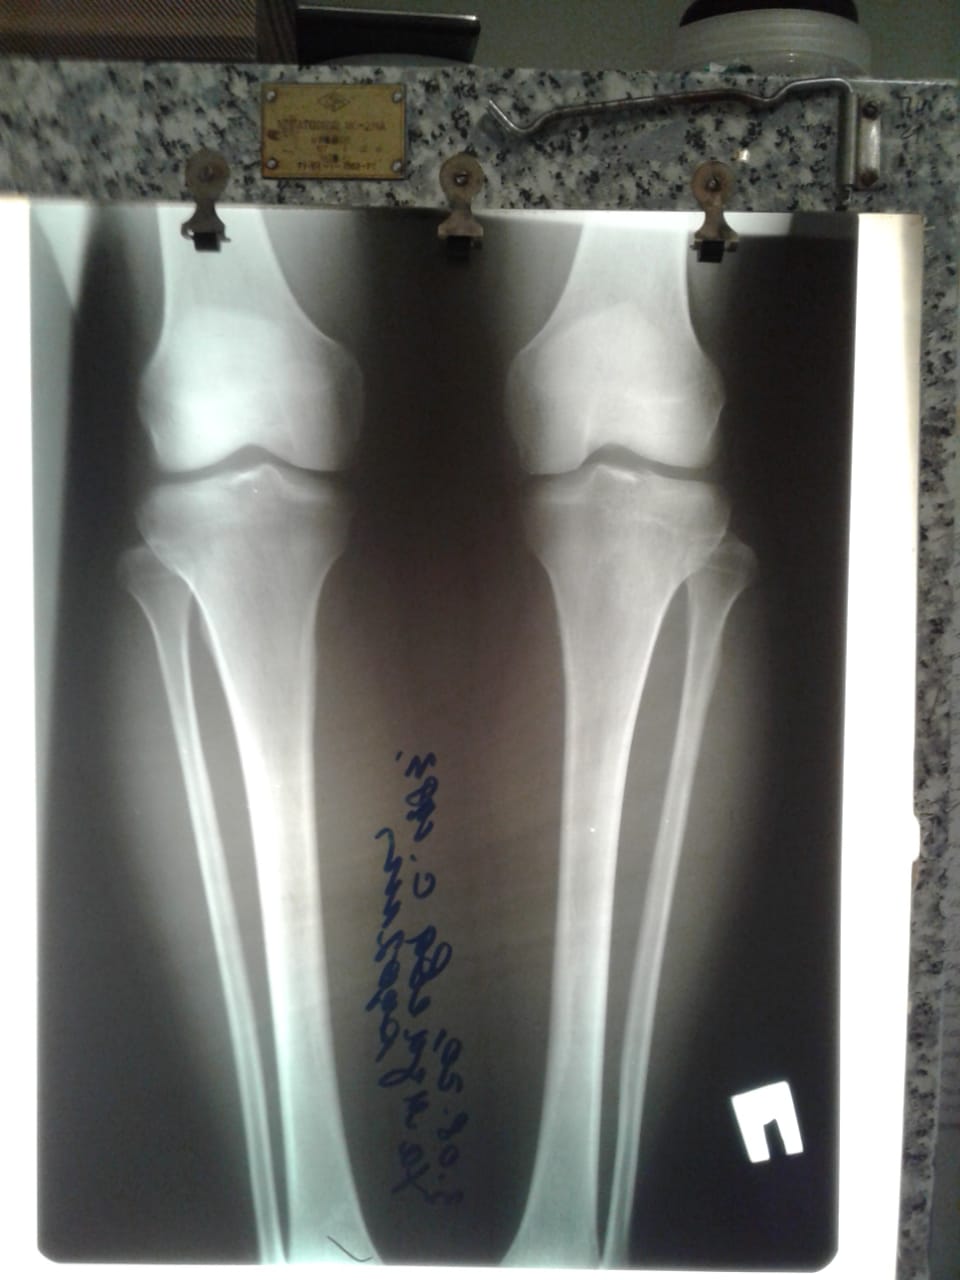

Исходник - 54 года.

Дата операции - 05.08.2020

image-21-08-20-12-33.jpg

image-04-08-20-09-41-5.jpeg